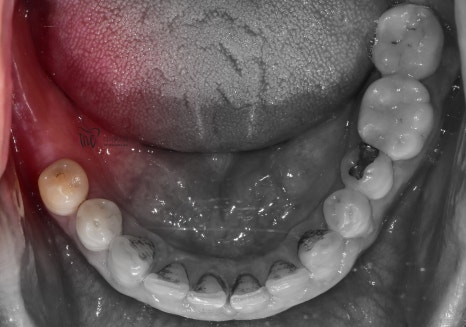

구강내 사진에서도, 아직 잔존 치조골이

충분히 남아있는 것은 확인이 되나

이는 정확히 CT를 찍은 뒤에

네비게이션 임플란트 진단을 해야

정확히 말씀드릴 수 있는 상황이였습니다.

그래서, 당일 바로 네비게이션 임플란트 진단을

진행해봤으나 골질이 낮은거 이외에는 별다른

특이소견은 관찰되지 않았습니다.